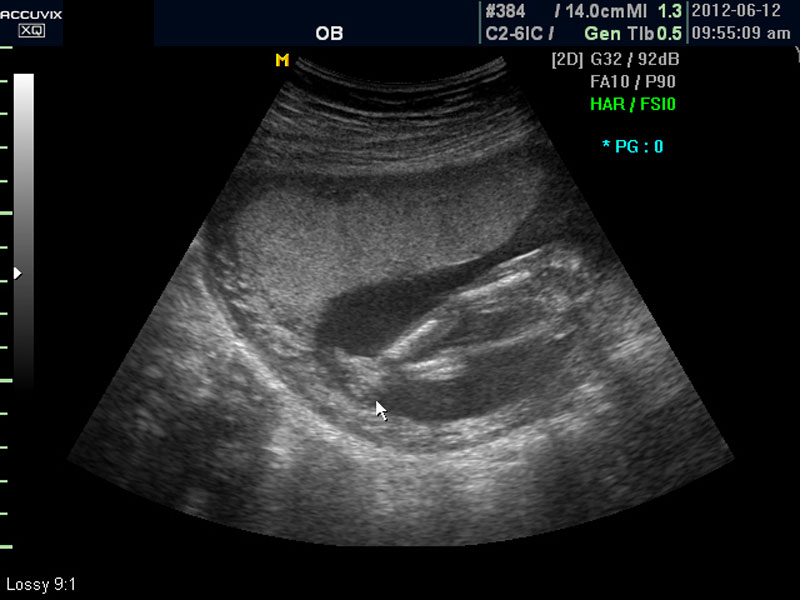

위 사진은 태아의 발바닥 사진인데 사진에서 보는 것처럼 그러나 이 시기는 손가락이나 발가락 또는  심장 내부의 구성 이상 등의 세세한 부분은 아직 크기가 작아서 제대로 확인하기 어려운 시기입니다.

따라서 부분 부분 살펴 보면서 해당 모습을 찍어서 저장하거나 인쇄하여 드리기도 하는 것이며 아래 사진은 태아의 다리 부분을 찍은 것입니다.